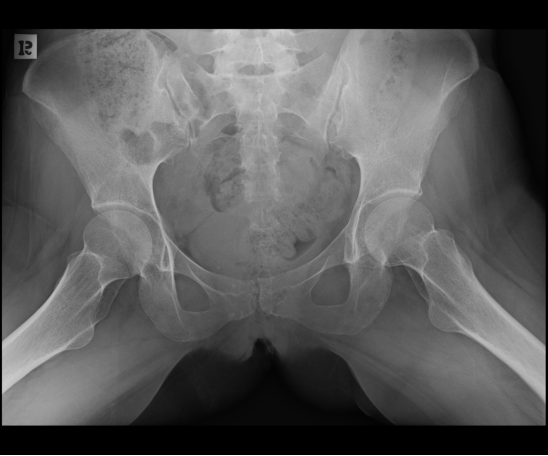

X线检查:

由于此病多由老年人骨质疏松症导致骶骨骨折,很多老年患者这种腰痛常常会被误诊为其他腰痛的原因,如,椎间盘突出/腰肌劳损等。此外,这种骨折通过骨盆 X 线平片很难发现骶骨骨折;特别是骶骨轻微移位的不全骨折大多无法判断。故诊断这种骨折的最佳方式是CT+磁共振检查。

2、单侧或双侧骶骨翼骨皮质断裂,见迂曲纵行骨折线,大致与骶髂关节平行(双侧多见);

3、骶骨体部看见骨折线

4、冠状位上述骨折形成 “H”型 ,故有人称东风本田征(为了方便记忆)

CT影像表现

东风本田征,较为特异性影像表现(冠状位重建)